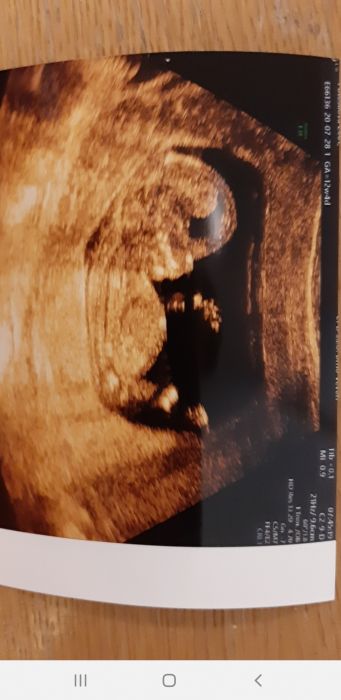

[474688] Já ani nepoznám, co to na té fotce je??? To jsou nohy? mezinoží?

[477996]

MikiV - Ano, Ano,

je to pohled přímo mezi nožičky